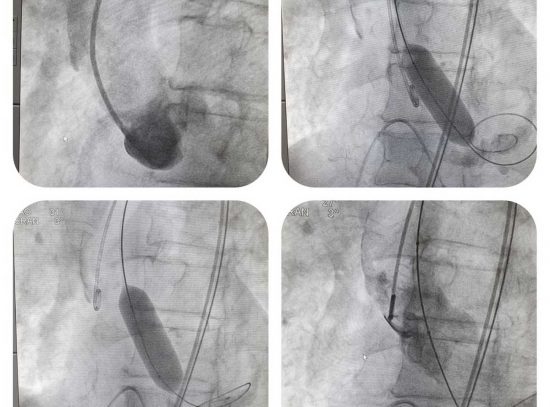

Viterbo – Riceviamo e pubblichiamo – Ieri, presso il laboratorio di Emodinamica, è stata eseguita a Belcolle la prima valvuloplastica aortica per via percutanea.

La procedura, effettuata dal direttore dell’unità operativa di Cardiologia, Luigi Sommariva, e dall’intero staff medico, infermieristico e tecnico del laboratorio, è sostanzialmente consistita nella dilatazione con un palloncino, della valvola aortica severamente malata e ristretta.

“L’intervento – spiega Luigi Sommariva – è avvenuto su un paziente di 80 anni con una serie di comorbidità che, di fatto, ne condizionavano la scelta chirurgica. È l’ennesimo tassello dell’offerta terapeutica in cardiologia interventistica anche per il trattamento di patologie tempo dipendenti, consentendo nel breve periodo l’erogazione della terapia anche in condizioni cliniche di emergenza.

“La dilatazione della valvola, come quella praticata oggi – conclude Sommariva -, consente al paziente di guadagnare tempo prezioso per la definizione del progetto terapeutico ulteriore, laddove si rendesse indicato. L’utilizzo routinario della valvuloplastica, a breve, consentirà di trattare anche quelle condizioni di emergenza che lo richiederanno”.